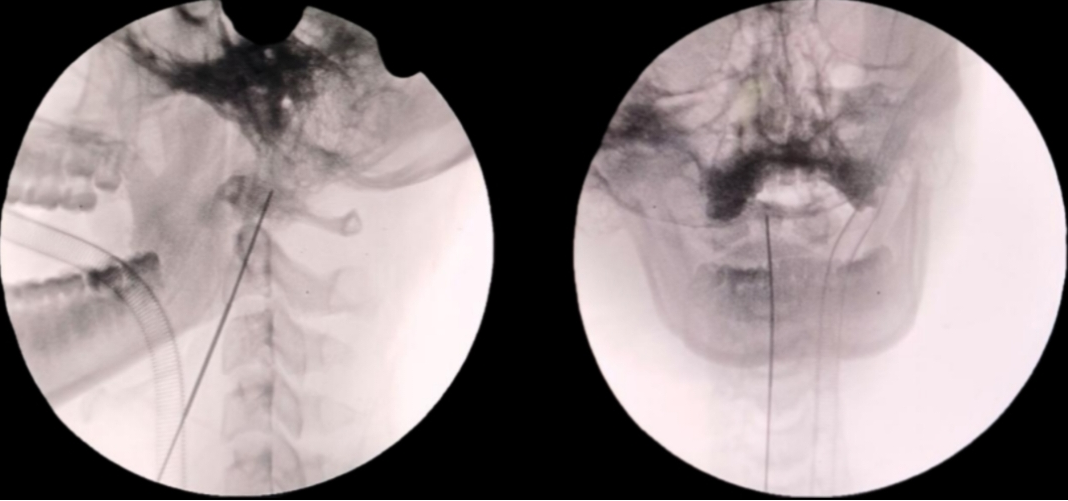

精准定位:小王平躺着,头和脖子轻轻后仰,C 臂机像 「实时摄像头」 一样,清晰显示颈椎情况,牢牢锁定齿状突骨折的位置;

插入导针:靠着透视 「导航」 找到齿状突基底部的位置,从 C2 椎体前下缘中点,将 1.2 毫米的导针,朝着齿状突尖部的方向插进去。

牢固固定:先量好导针深度,选长度适配的空心螺钉,顺着导针钻孔、攻丝后,再将钛合金空心螺钉稳稳装进去——装完后再用透视确认:螺钉跨过骨折线,把骨折部位牢牢 「锁」 住;